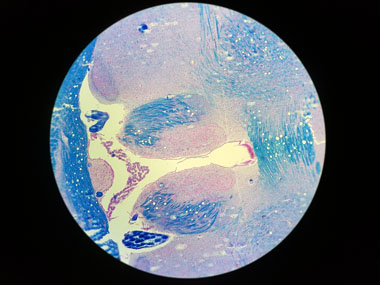

Blickt man durch das Okular in ein Mikroskop, sieht man ein kreisrundes Bild. Beim Fotografieren durch ein Mikroskop wird jedoch ein rechteckiger Sensor belichtet. Zur Vermeidung von Randabschattungen durch den runden Bildrand, fotografiert man deshalb einen rechteckigen Ausschnitt, der im besten Fall so gewählt ist, dass der dunkle Rand gerade außerhalb des fotografierten Bildes liegt.

Nur mit einer sehr guten Optik sieht man im Okular des Mikroskops ein Bild, das von der Mitte bis zum äußersten Bildrand scharf und ohne Farbsäume ist. In allen anderen Fällen ist die Bildqualität in der Mitte am höchsten und lässt qualitativ in einem mehr oder weniger breiten Bereich am Bildrand nach.

Aus diesem Grunde wählt man den zu fotografierenden Ausschnitt so, dass die Ecken des Rechtecks nicht ganz den Bildrand erreichen, damit die dort vorhandene mindere Bildqualität nicht auf dem Foto zu sehen ist.

Oben links: Volles Bild im Okular Oben rechts: Darstellung des korrekten Beschnitts des kreisrunden Bildes Unten rechts: Foto mit korrekter optischer Adaption |